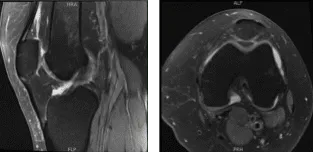

She was in the office with MRI results that showed complex multidirectional tear free edge lateral meniscus on the background of mild lateral compartment osteoarthritis. Mild patellofemoral compartment osteoarthritis as well.

MRI-3 Left knee non-contrast

Examination of the lateral tibiofemoral compartment showed tear of the posterior horn and body of the lateral meniscus along with grade 3 to grade 4 osteochondral lesion. Debridement of the meniscus as well as the cartilage was done with the use of biters and shavers. Balanced edges could be achieved.